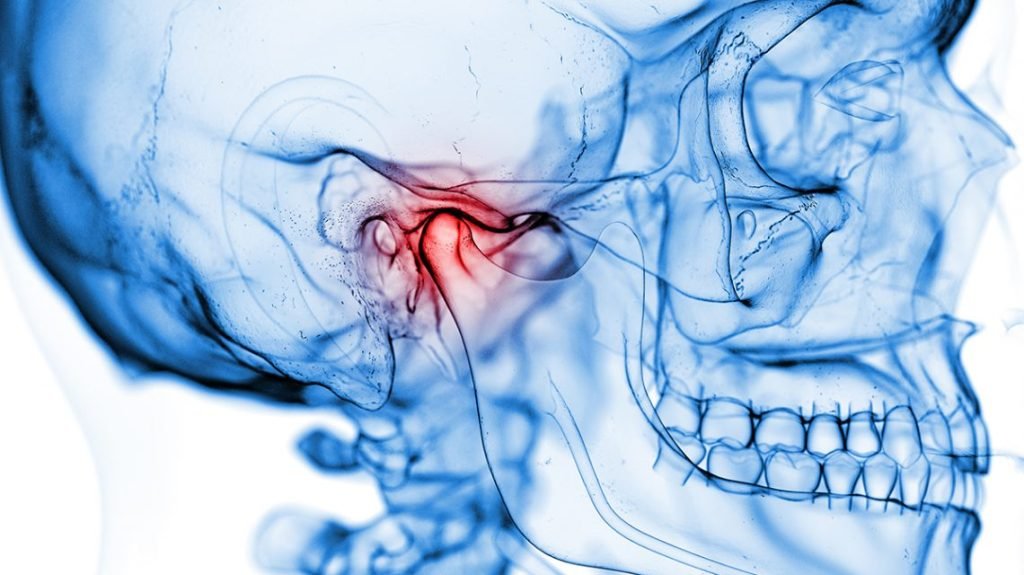

Relieve jaw pain, clicking sounds, and bite discomfort caused by temporomandibular joint disorders.

We provide advanced TMJ evaluation, bite correction therapy, and personalized treatment plans designed to improve jaw function, reduce muscle tension, and restore long-term comfort with stable, balanced results.